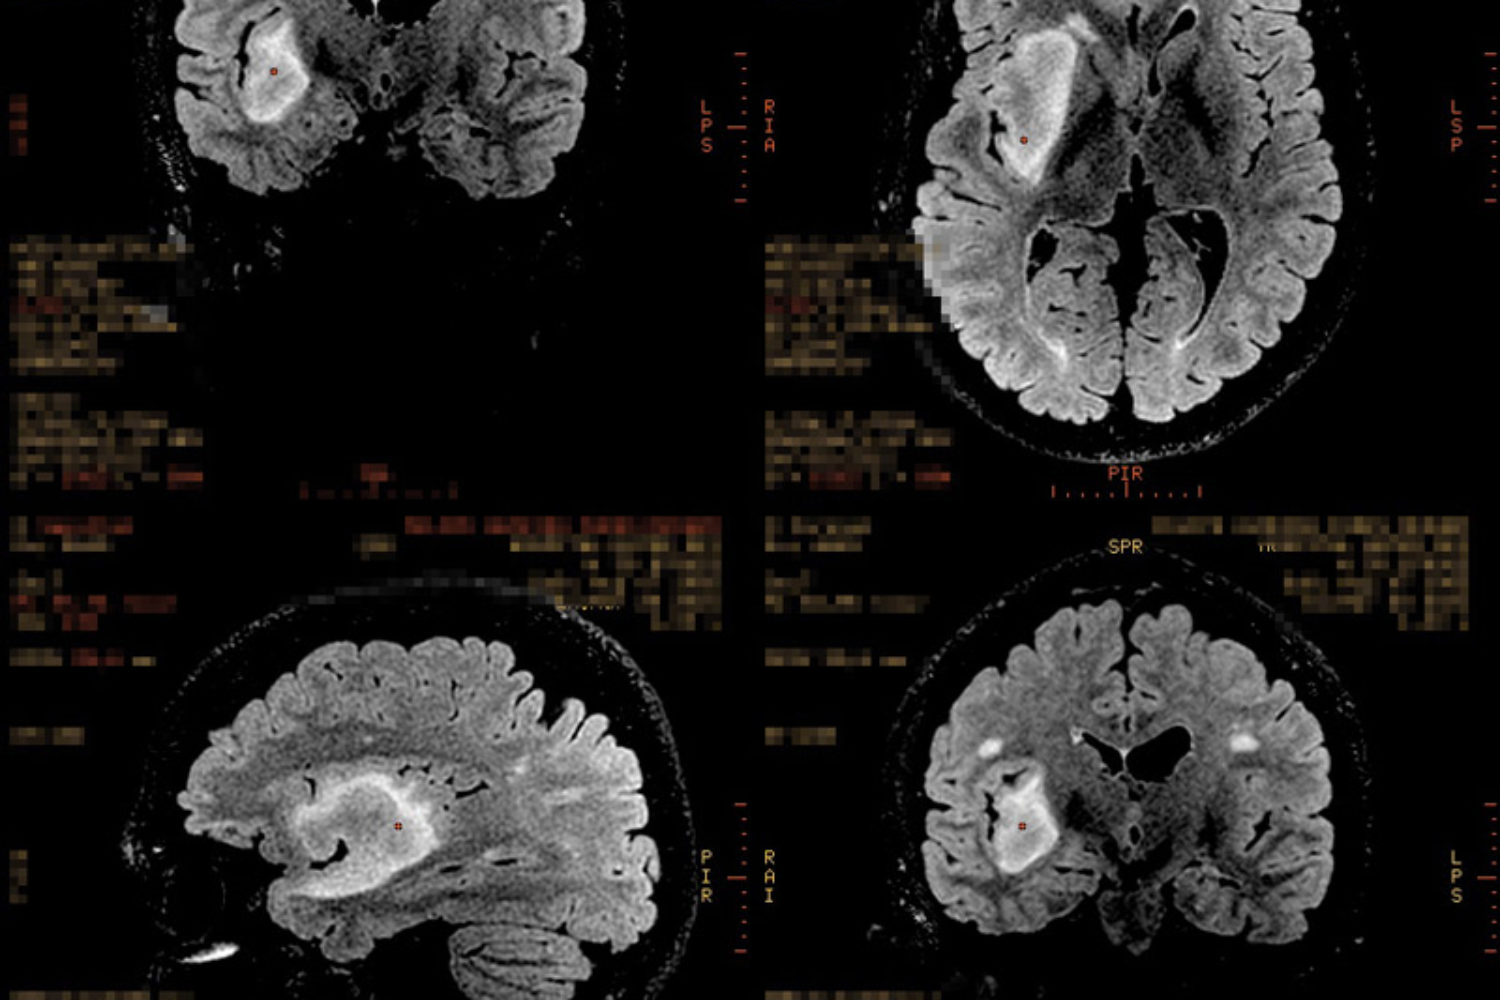

Desbloqueei um exame novo no meu repertório: eletroencefalograma. Nunca tinha feito até ontem.